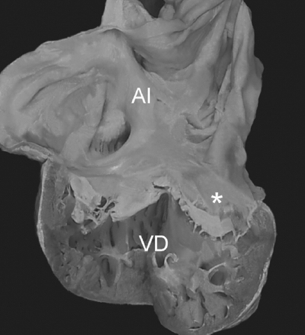

Figura 1 Vista interna de las cámaras derechas de un corazón con concordancia auriculoventricular y anomalía de Ebstein de la válvula tricúspide. El anillo fibroso está situado en la unión auriculoventricular (asteriscos). Obsérvese el adosamiento de las valvas septal y posterior a las paredes ventriculares, la valva anterior es redundante. AD: aurícula derecha; I: infundíbulo; VA: válvula anterior; VD: ventrículo derecho; VP: válvula posterior; VS: válvula septal.